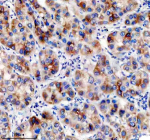

Immunohistochemical staining of TNFRSF10D using anti-TNFRSF10D antibody. TNFRSF10D was detected in a paraffin-embedded section of human liver cancer tissue. Heat mediated antigen retrieval was performed in EDTA buffer (pH 8.0, epitope retrieval solution). The tissue section was blocked with 10% goat serum. The tissue section was then incubated with 2 ug/ml rabbit anti-TNFRSF10D antibody overnight at 4oC. Peroxidase Conjugated Goat Anti-rabbit IgG was used as secondary antibody and incubated for 30 minutes at 37oC. The tissue section was developed using an HRP secondary and DAB substrate.